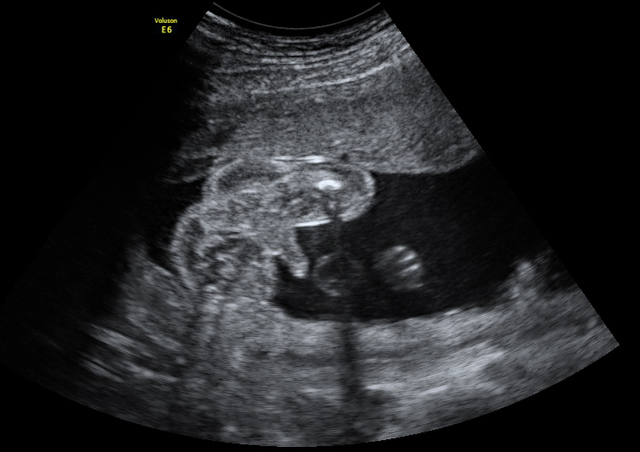

Feto 9 sem

• PLIEGUE NUCAL

PLIEGUE NUCAL

Entre las semanas 11 y 14 es muy importante, además de la revisión sistemática, medir el PLIEGUE NUCAL, para descartar enfermedades cromosómicas, como el SINDROME DOWN